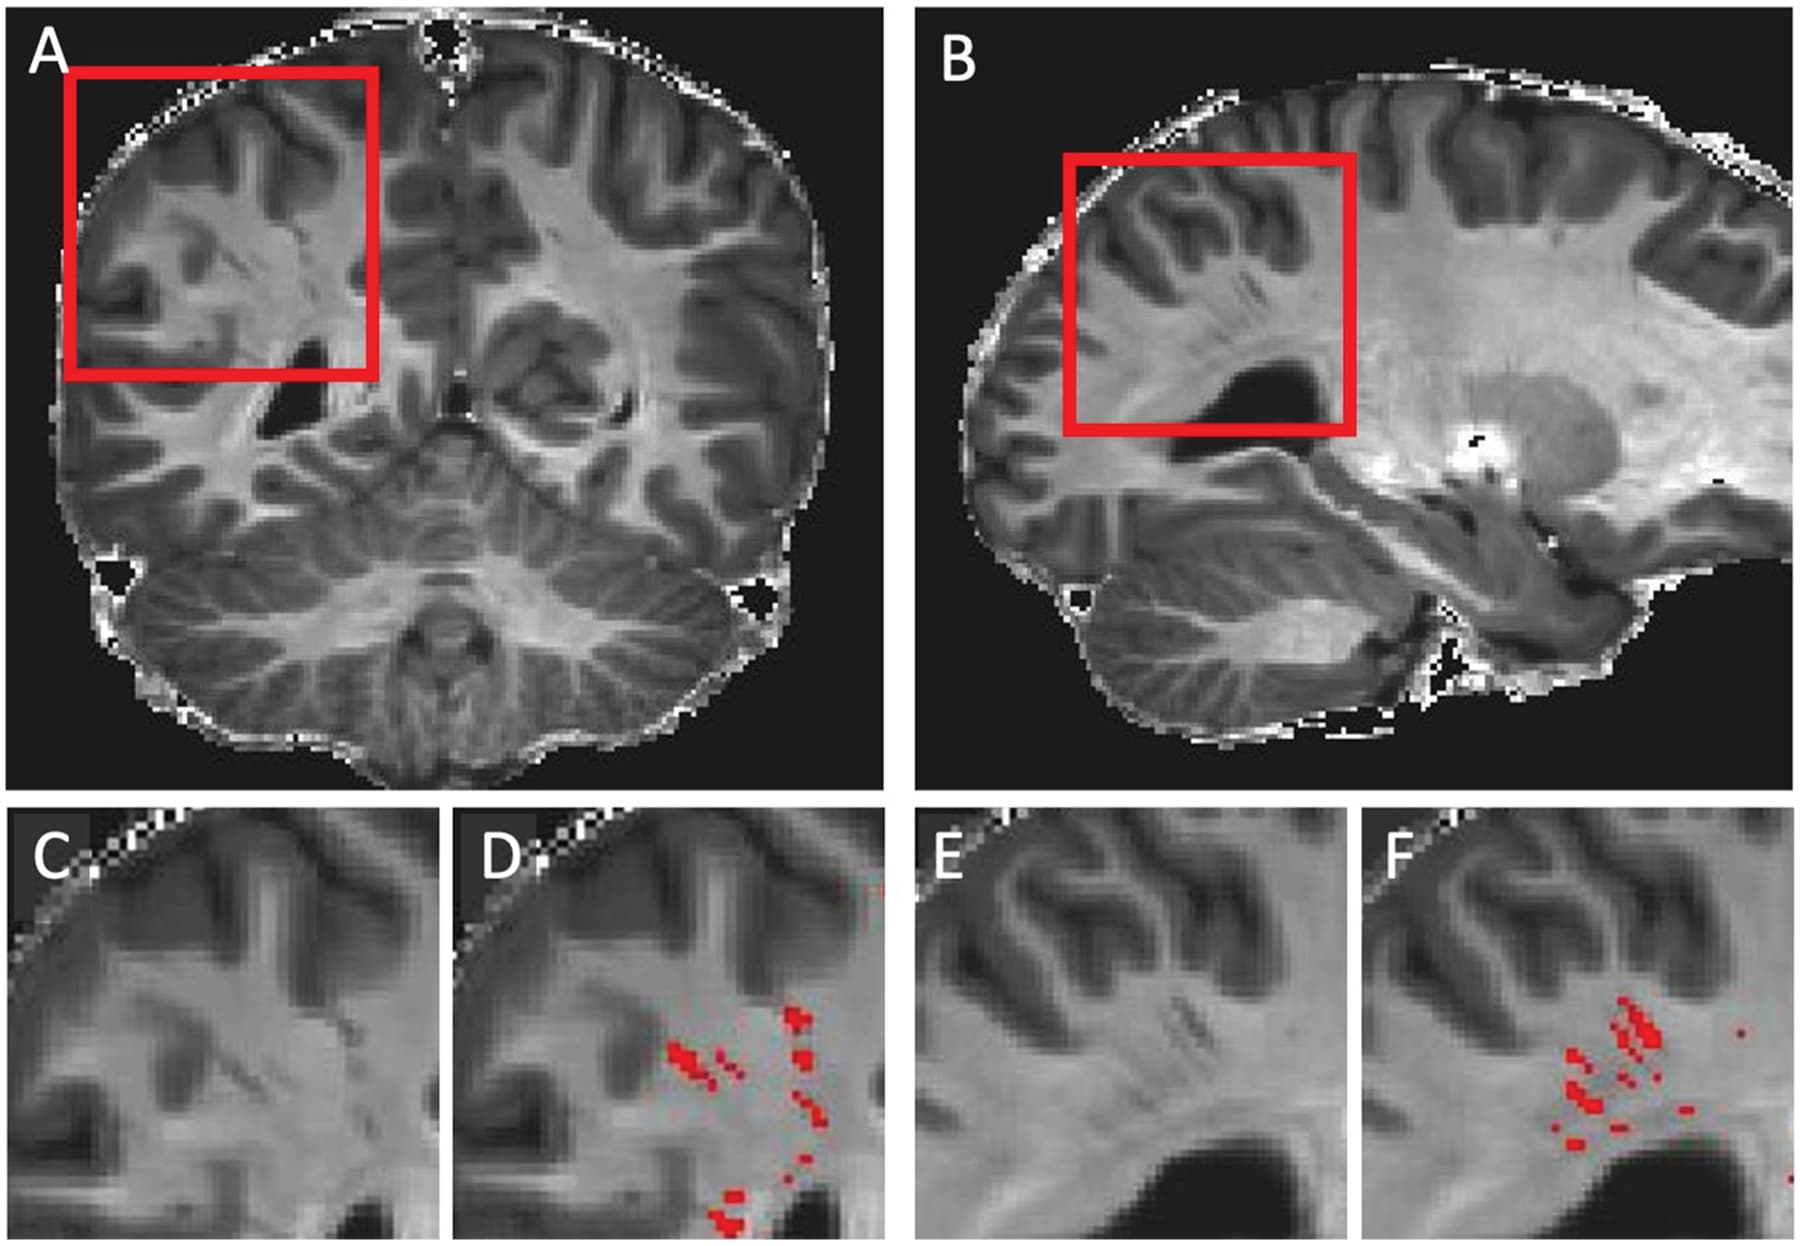

note MRI‐visible dilated perivascular spaces in healthy young adults: A twin heritability study - PMC has false positive reduction

In our study, frequency distribution of WM-PVS grades according to different severity levels of ASD shows an increasing trend, with 80% “mild” ASD patients with less than 40 WM-PVS (WM-PVS grade 0–3) in a single MRI section and 53% “severe” ASD patients with more than 40 visible WM-PVS (WM-PVS grade 4). Consistently, patients with ASD and insomnia tend to have higher WM-PVS volume compared to ASD patients without sleep issues, although this result was not statistically significant. Previous studies reported an association between higher PVS visibility on MRI and impaired sleep quality and efficiency (Berezuk et al., 2015; Aribisala et al., 2020) and obstructive sleep apnea (Song et al., 2017). In fact, sleep has been shown to be important for a proper functioning of the glymphatic system (Hablitz and Nedergaard, 2021).

Moreover, PVS dilation is significantly associated with a younger age in ASD patients (less than 4 years in our study). This finding is of particular importance as it corroborates the aforementioned age-related GS dysfunction in patients with ASD studied with DTI-ALPS MRI (Li et al., 2022) and the transient excess volume of EA-CSF in children who have been diagnosed as ASD later in their life (Shen et al., 2018).

^this says more (smaller) PVS associated with slower grey matter decline.